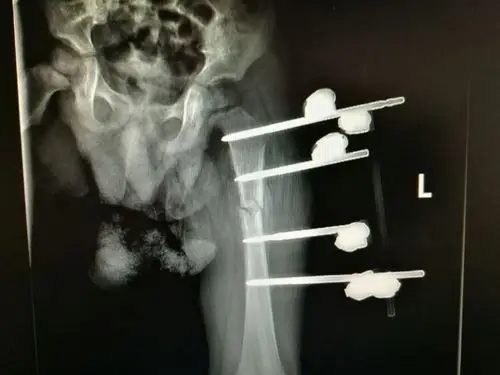

一例骨折愈合欠佳患者的愈合之路!

经过1个月的治疗后复查片可见骨折端对位对线良好,可见大量骨痂生长.

闭合复位外固定支架治疗2岁儿童股骨干骨折(副本)